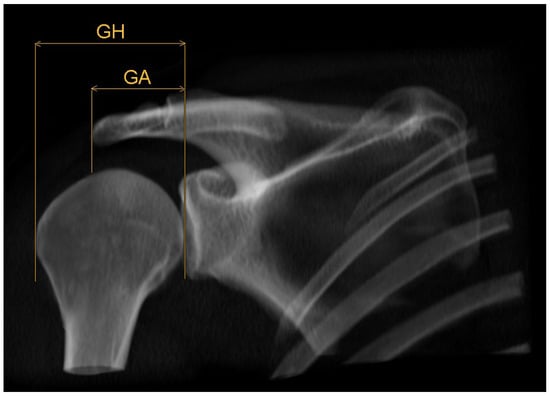

2.3. Acromion Index (Figure 1)